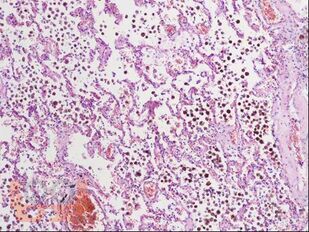

В пособии представлены цветные иллюстрации микропрепаратов и соответствующее им морфологическое описание. Детально освещены основные, наиболее важные гистологические изменения внутренних органов, позволяющие на светооптическом уровне диагностировать и дифференцировать между собой разнообразные патологические состояния. Представлены микрофотографии с гистохимическими окрасками различных тканей, использование которых помогает верифицировать специфические патологические процессы.